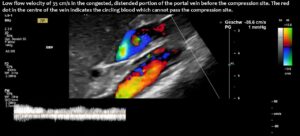

Compression of the superior mesenteric vein and its distension not only compresses the duodenum, but also reduces venous return from the small bowel, which can impair food absorption. Blocked blood flow at the compression site can be demonstrated by a whirling blood stream in front of the compression. Subsequent layers demonstrate antegrade and retrograde flow, as can be seen in the layering of blue and red flow inside the enlarged vein, pointing to changing flow directions and the different flow directions in these layers as highlighted by the spectral analyses at the bottom of the image.